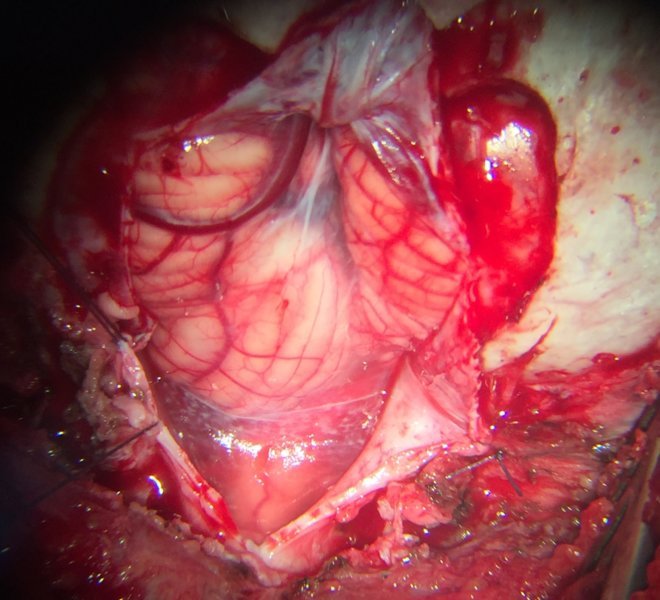

MEDULOBLASTOMA

DESCRIPCIÓN